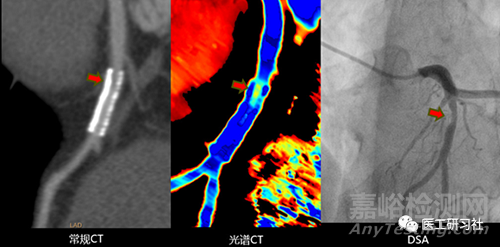

能量CT精確評價支架內(nèi)再狹窄(來自互聯(lián)網(wǎng))

雖然上述方法在技術(shù)實現(xiàn)上存在巨大差異,但基本都成功地獲得了雙能后處理應(yīng)用所需的成對高/低能x射線吸收數(shù)據(jù)。

鑒于能量CT對腫瘤早發(fā)現(xiàn)、冠心病、大血管造影等疾病精準(zhǔn)診斷方面具有獨特價值,已經(jīng)被業(yè)界專家廣泛認(rèn)可,并成為臨床指南中的推薦掃描方式。